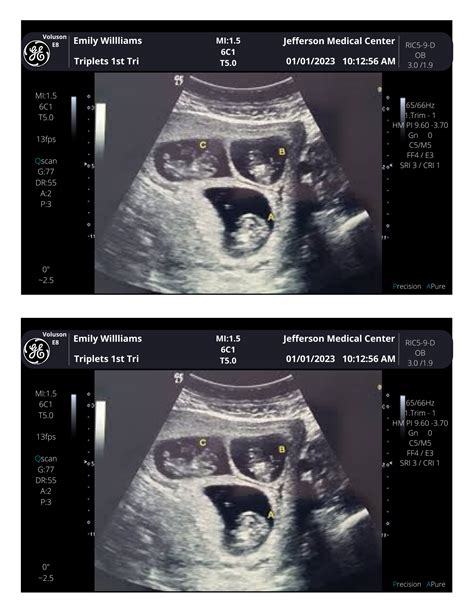

A sonogram is the image produced by ultrasound technology. It is essentially a visual representation of the internal structures of the body captured by ultrasound waves. Sonograms are used to diagnose a variety of conditions, including tumors, cysts, and other abnormalities. In the context of prenatal care, sonograms provide detailed images of the fetus, allowing healthcare providers to assess its development and detect any potential issues.

Sonograms can be performed at different stages of pregnancy, with each stage providing different insights. Early sonograms, often done around 6-8 weeks, can confirm the presence of a fetus and determine the gestational age. Later sonograms, typically around 18-22 weeks, offer more detailed images and can reveal the sex of the baby, as well as check for any structural abnormalities.